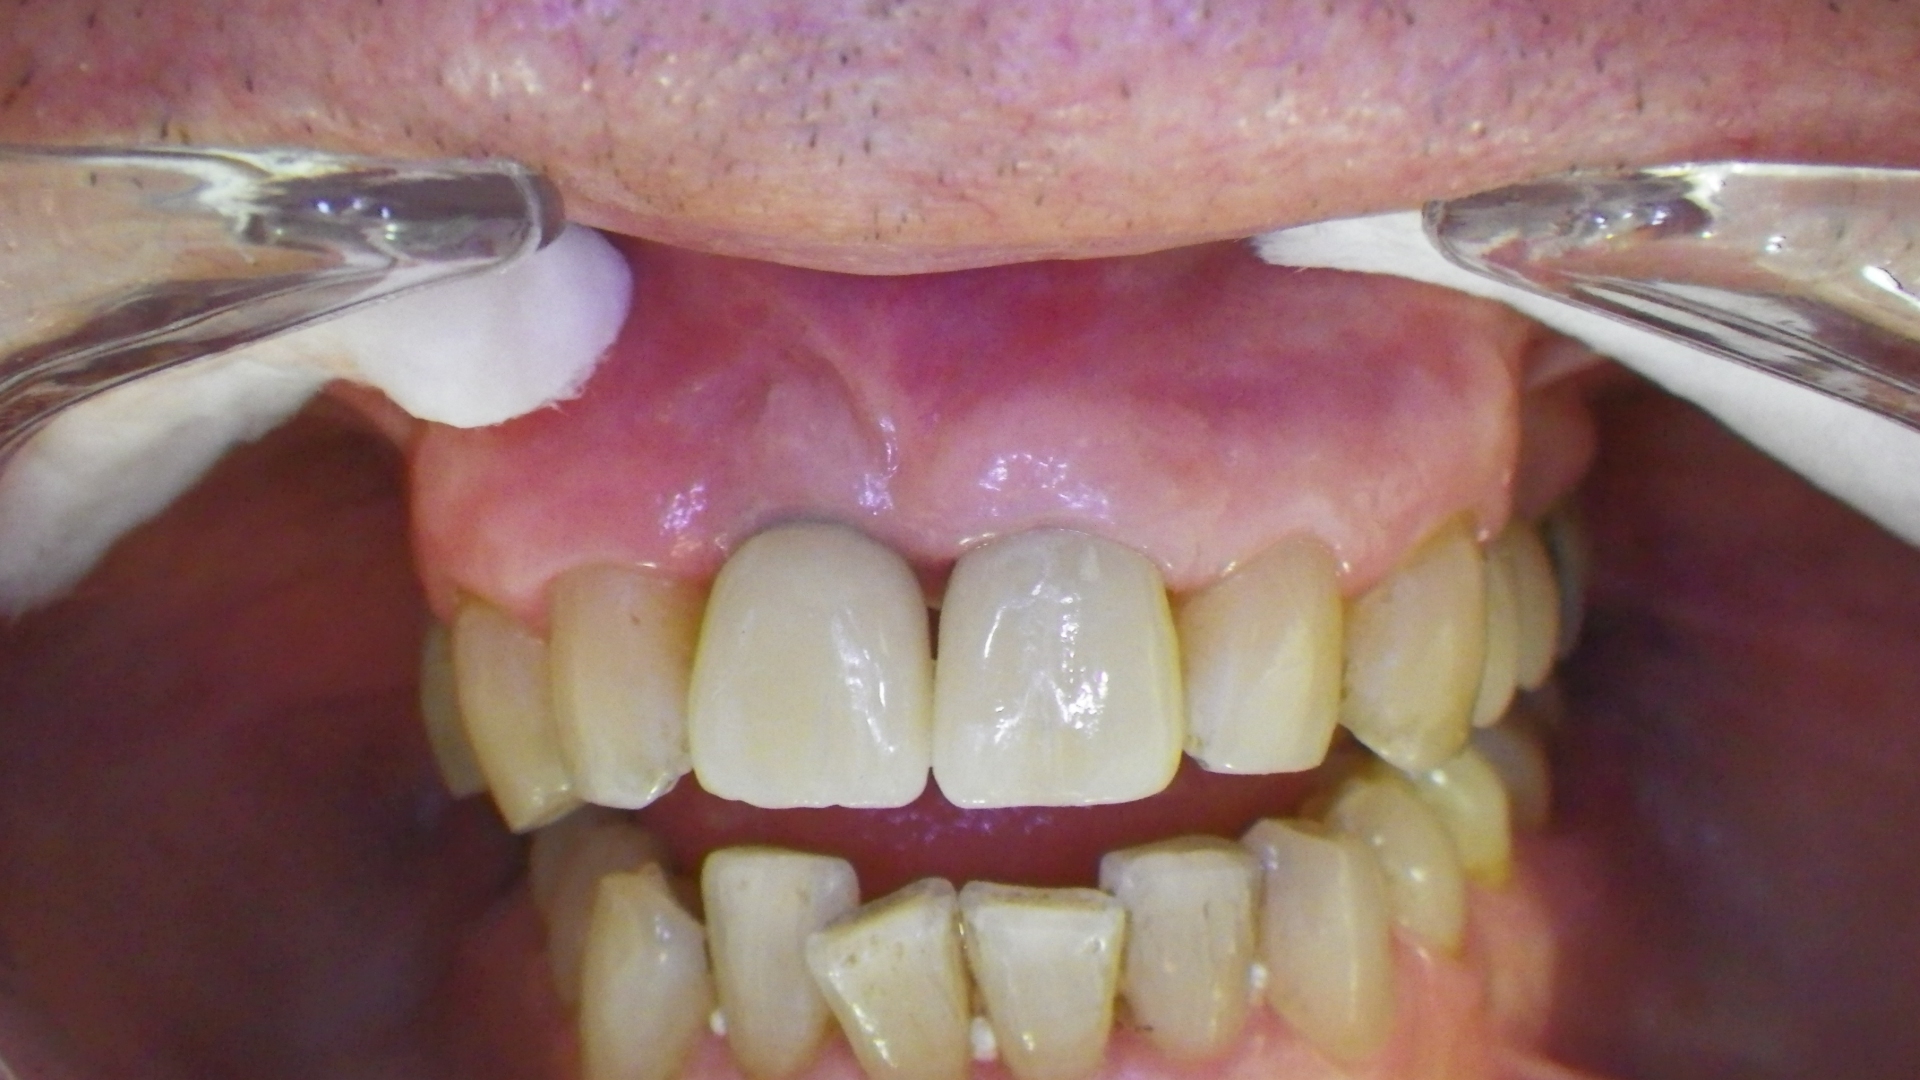

Este paciente llegó al consultorio con reabsorción dentinaria (pérdida de la estructura del diente). Por ello se le extrajo el diente, se le colocó un implante y se restauraron las piezas con coronas de cerámica pura.